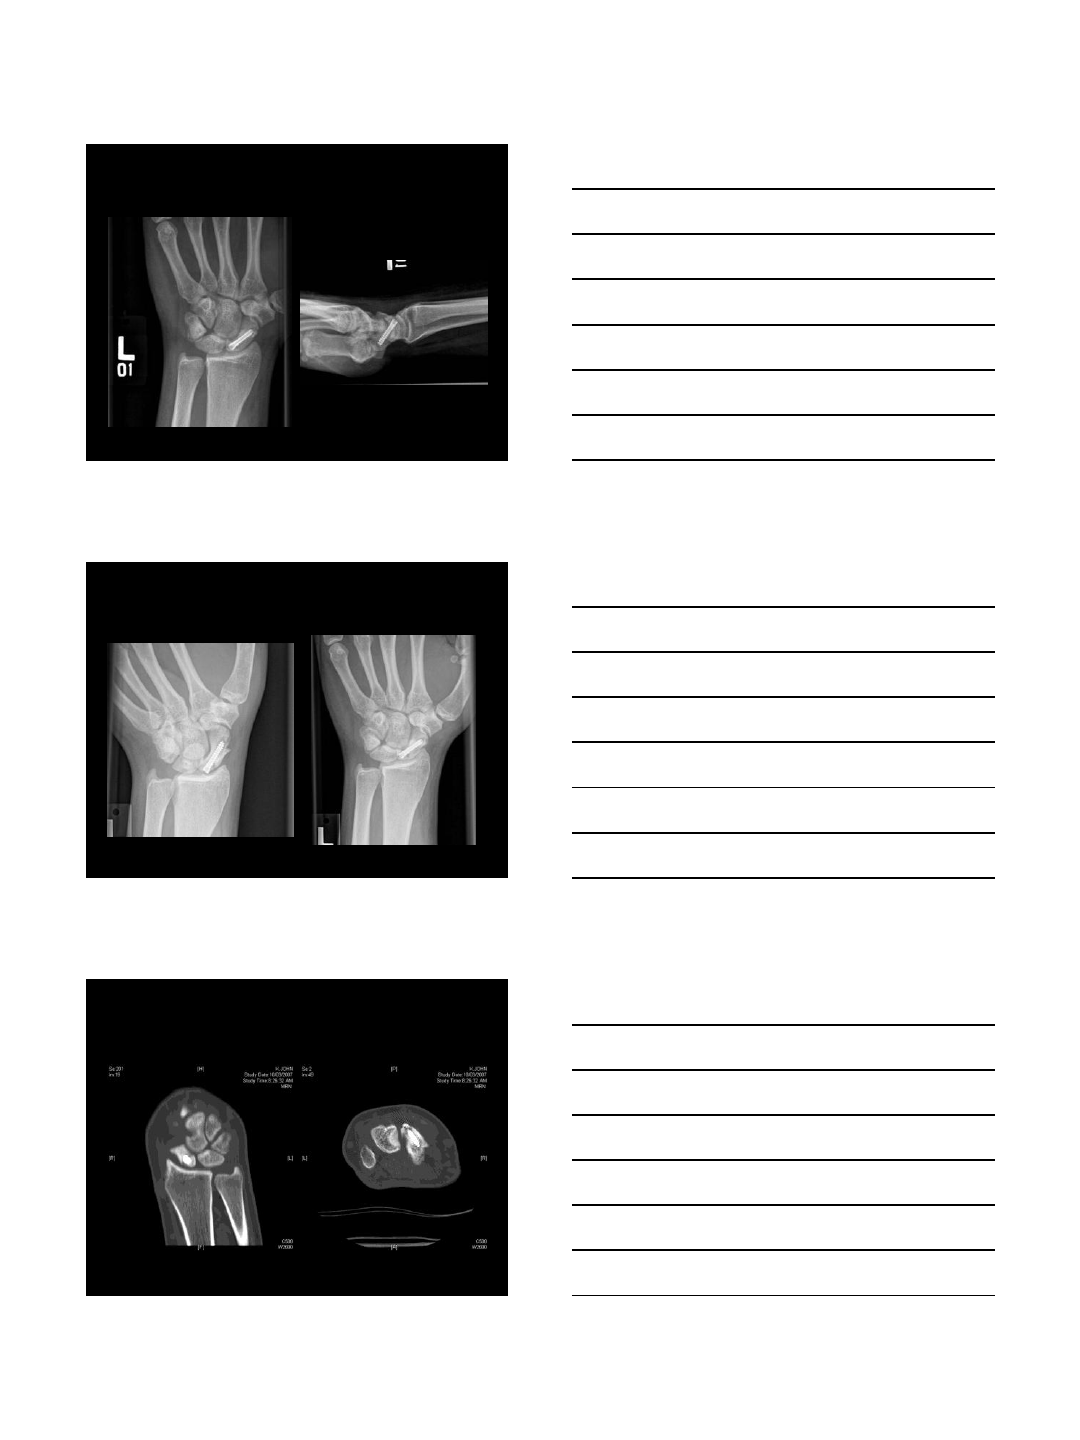

Initial Post-Op Xrays

5 Months Post-Op

5 Mos Post-Op CT

9/10/2013